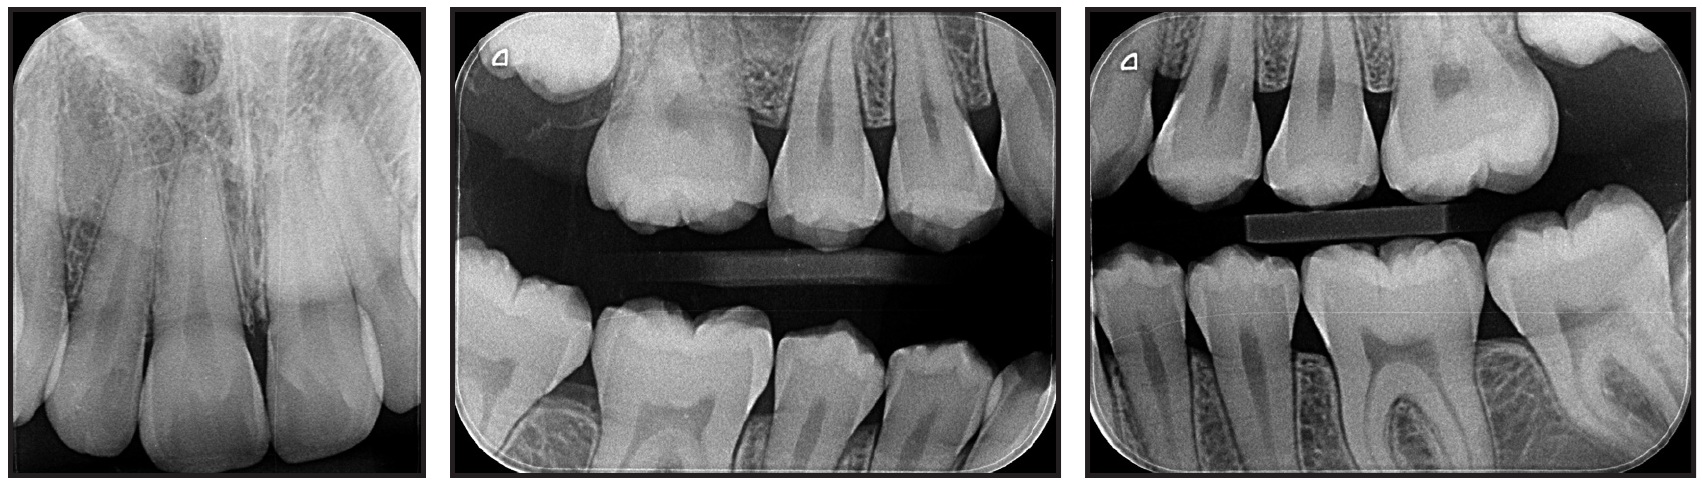

Clinical examination confirmed an anterior open bite extending from first premolar to first premolar, a bilateral Class I molar relationship, moderate lower anterior crowding, and excessive overjet. The panoramic radiograph revealed the presence of unerupted upper second and lower third molars and agenesis of the upper third molars. The upper second molars were favorably positioned for later eruption,36 with incomplete rhizogenesis (Fig. 6B). There was no deviation between centric occlusion and centric relation, and there were no signs of TMD. Cephalometric analysis found an anteroposterior maxillomandibular discrepancy with mandibular deficiency, a slightly vertical growth pattern with an excessive mandibular-plane angle, and a convex skeletal profile. The upper incisors were slightly protrusive, but the lower incisors were well positioned.

Fig. 6 (cont.) 13-year-old female patient with bilateral Class I molar relationship, anterior open bite, moderate lower anterior crowding, and excessive overjet before treatment.